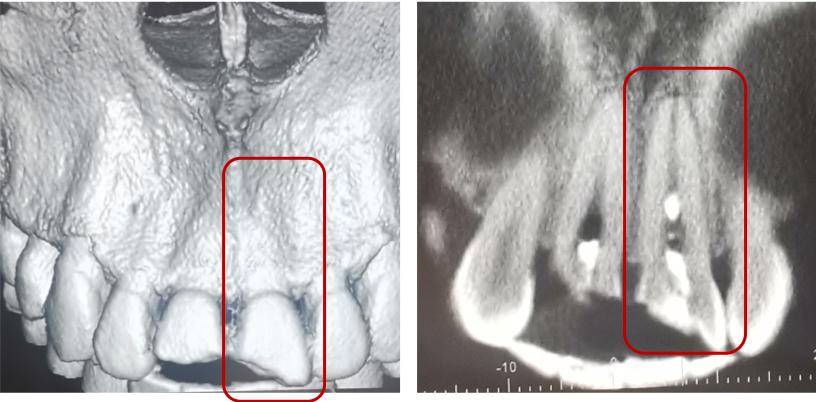

冠根折:累及牙釉质--牙本质--牙骨质折断,累及牙釉质--牙本质--牙骨质--牙髓折断

治疗方案:方案(1)正畸或外科牵引4mm+冠延长+根管治疗+桩核冠修复或根面覆盖;方案(2)拔除患牙后种植修复;方案(3)意向性再植;方案(4)自体牙移植。